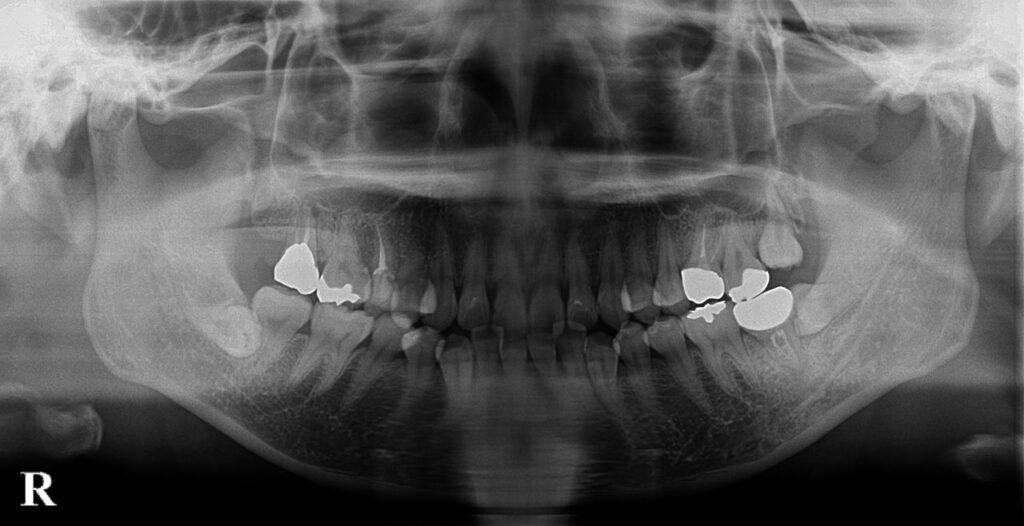

この方は右上の7番目の歯が歯根破折しており左上8を抜歯後右上7部分に移植した症例です。